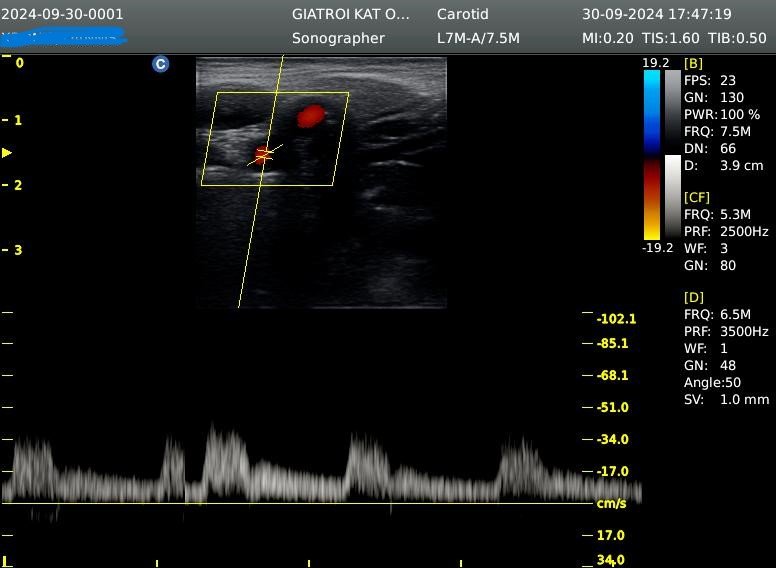

- Τρίπλεξ ( triplex ) καρωτίδων και σπονδυλικών αρτηριών κατ’ οίκον( πάχος ενδοθηλίου, έλεγχος για αθηρωτικές πλάκες, ποσοστό στένωσεις έσω καρωτίδων)